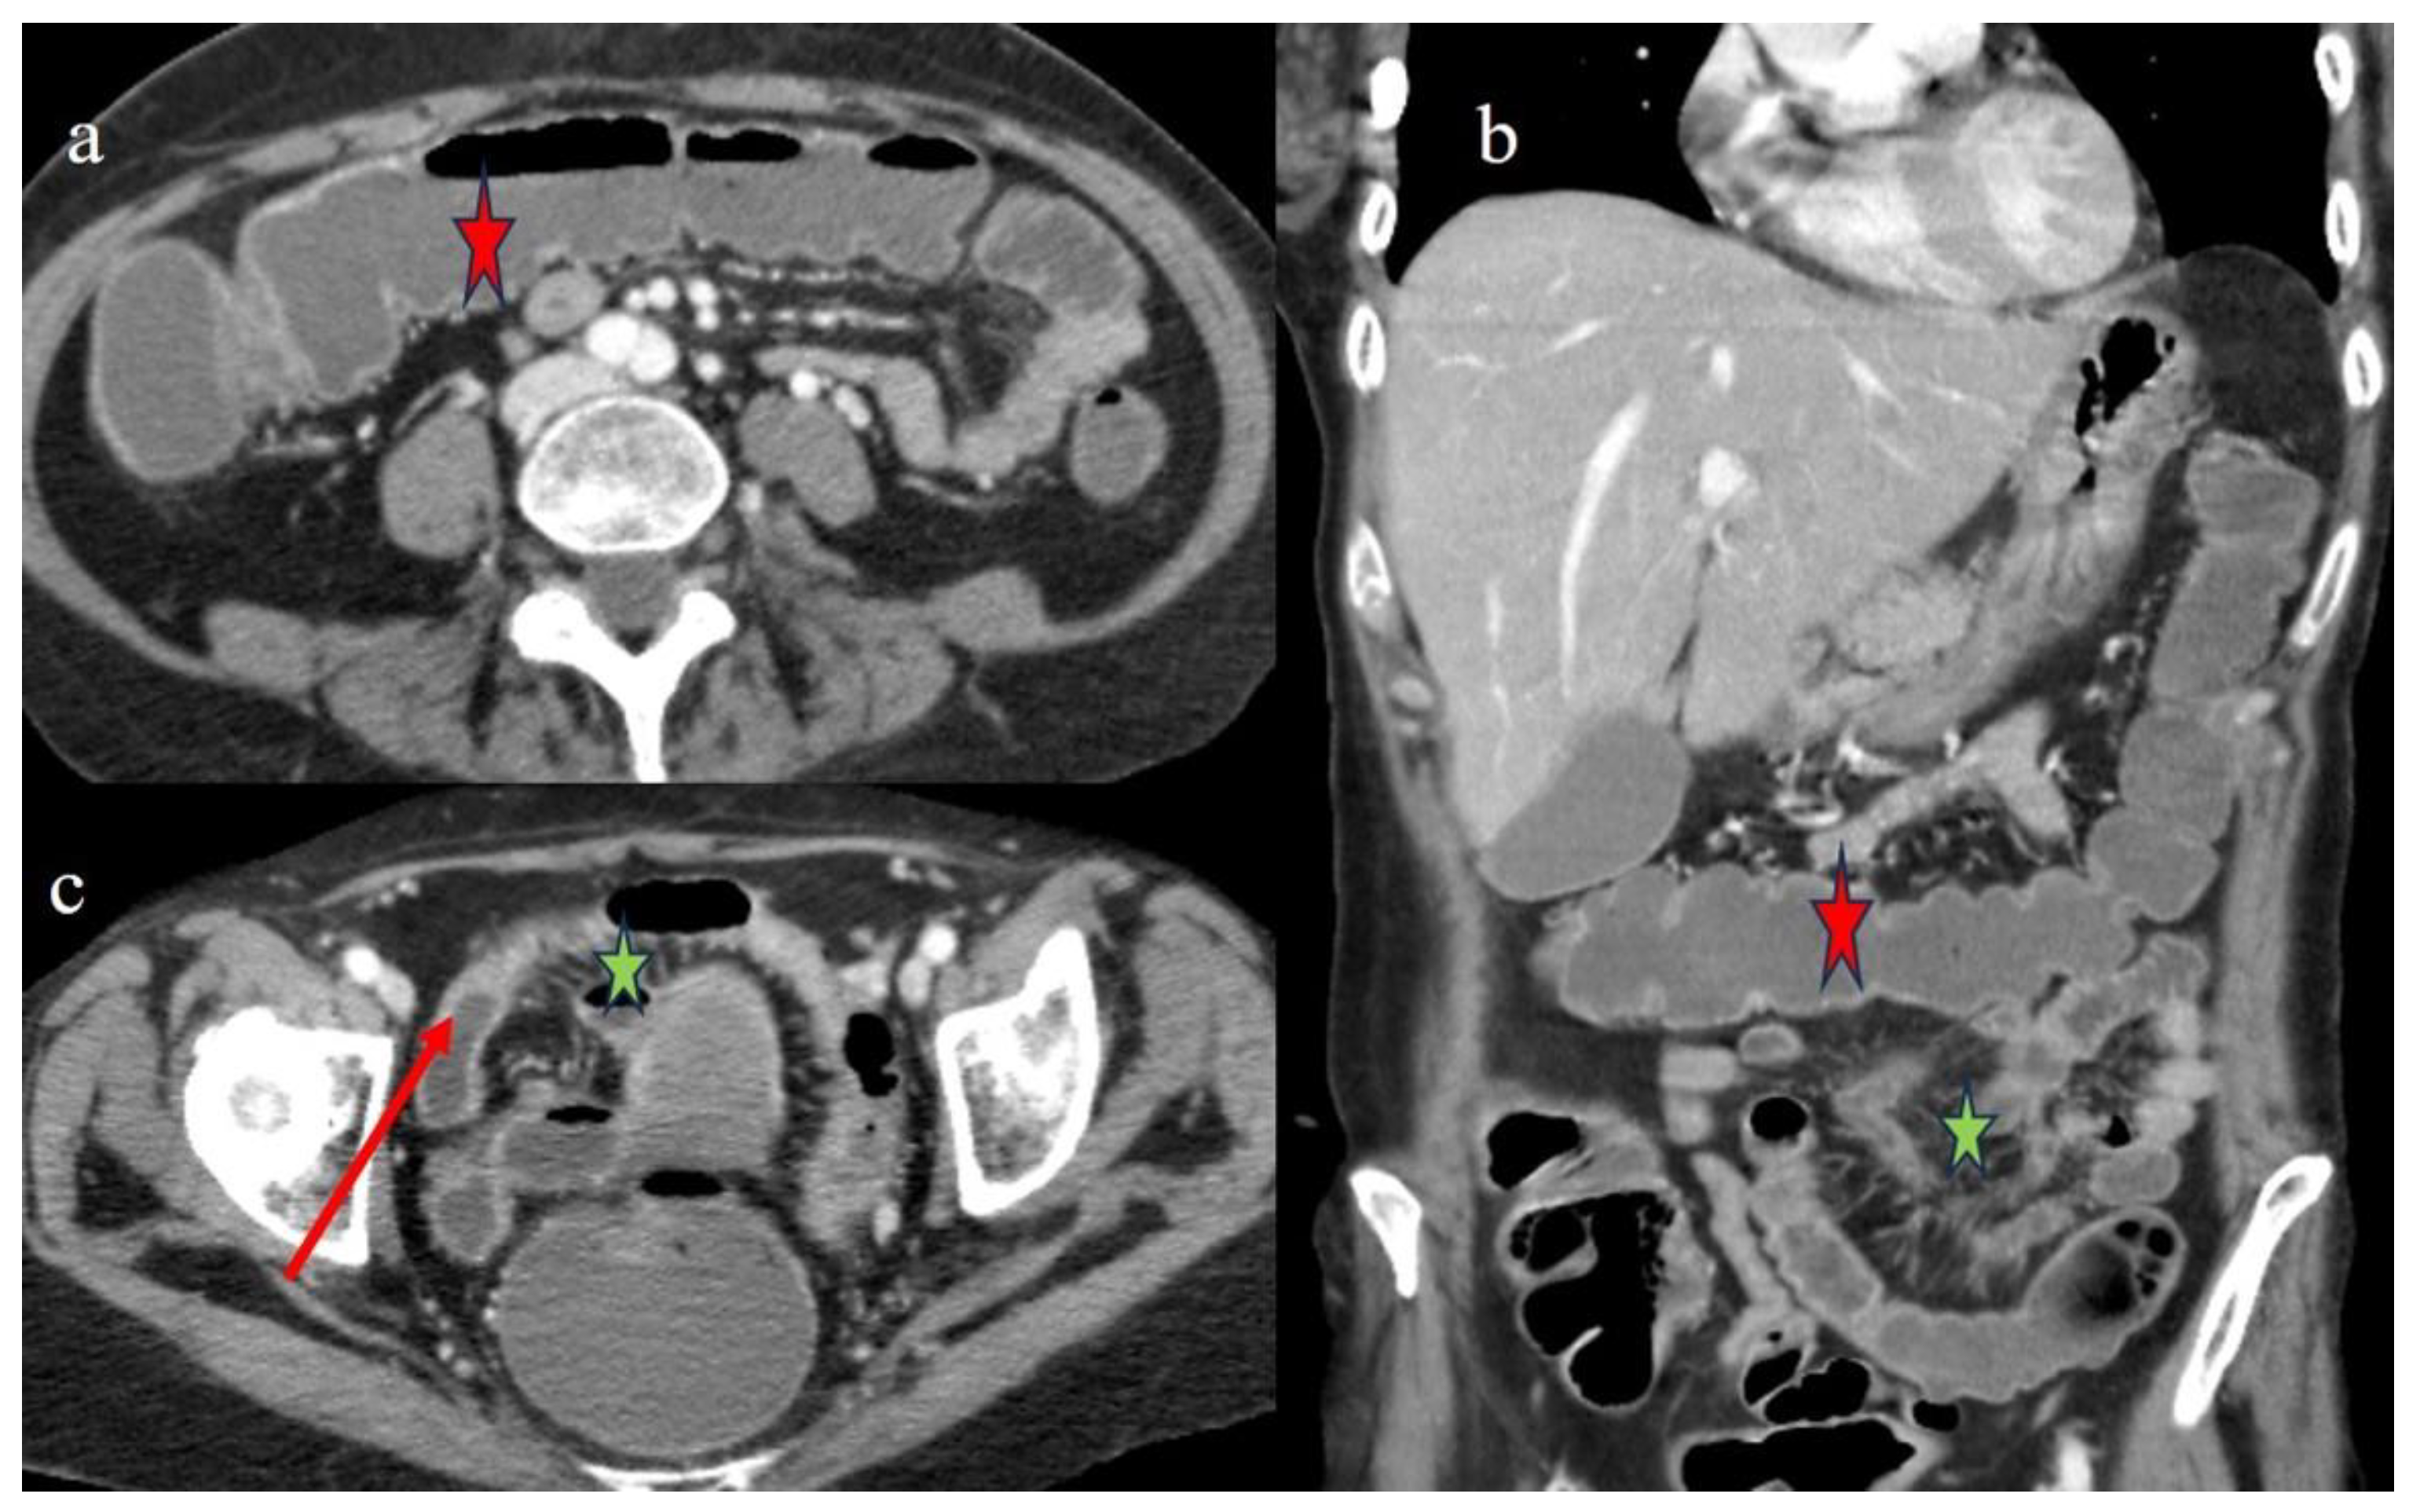

| 5 | P | P | Multisegmental thickness with stenosis on jejunal loops and SBO and segmental and focal thickness on the terminal ileus and appendix | Diffuse parietal thickness with stratified enhancement | Mild comb sign, poor reactive mesenteric lymph node, small air bubbles in the ascites | Small splenic areas of ischemia |